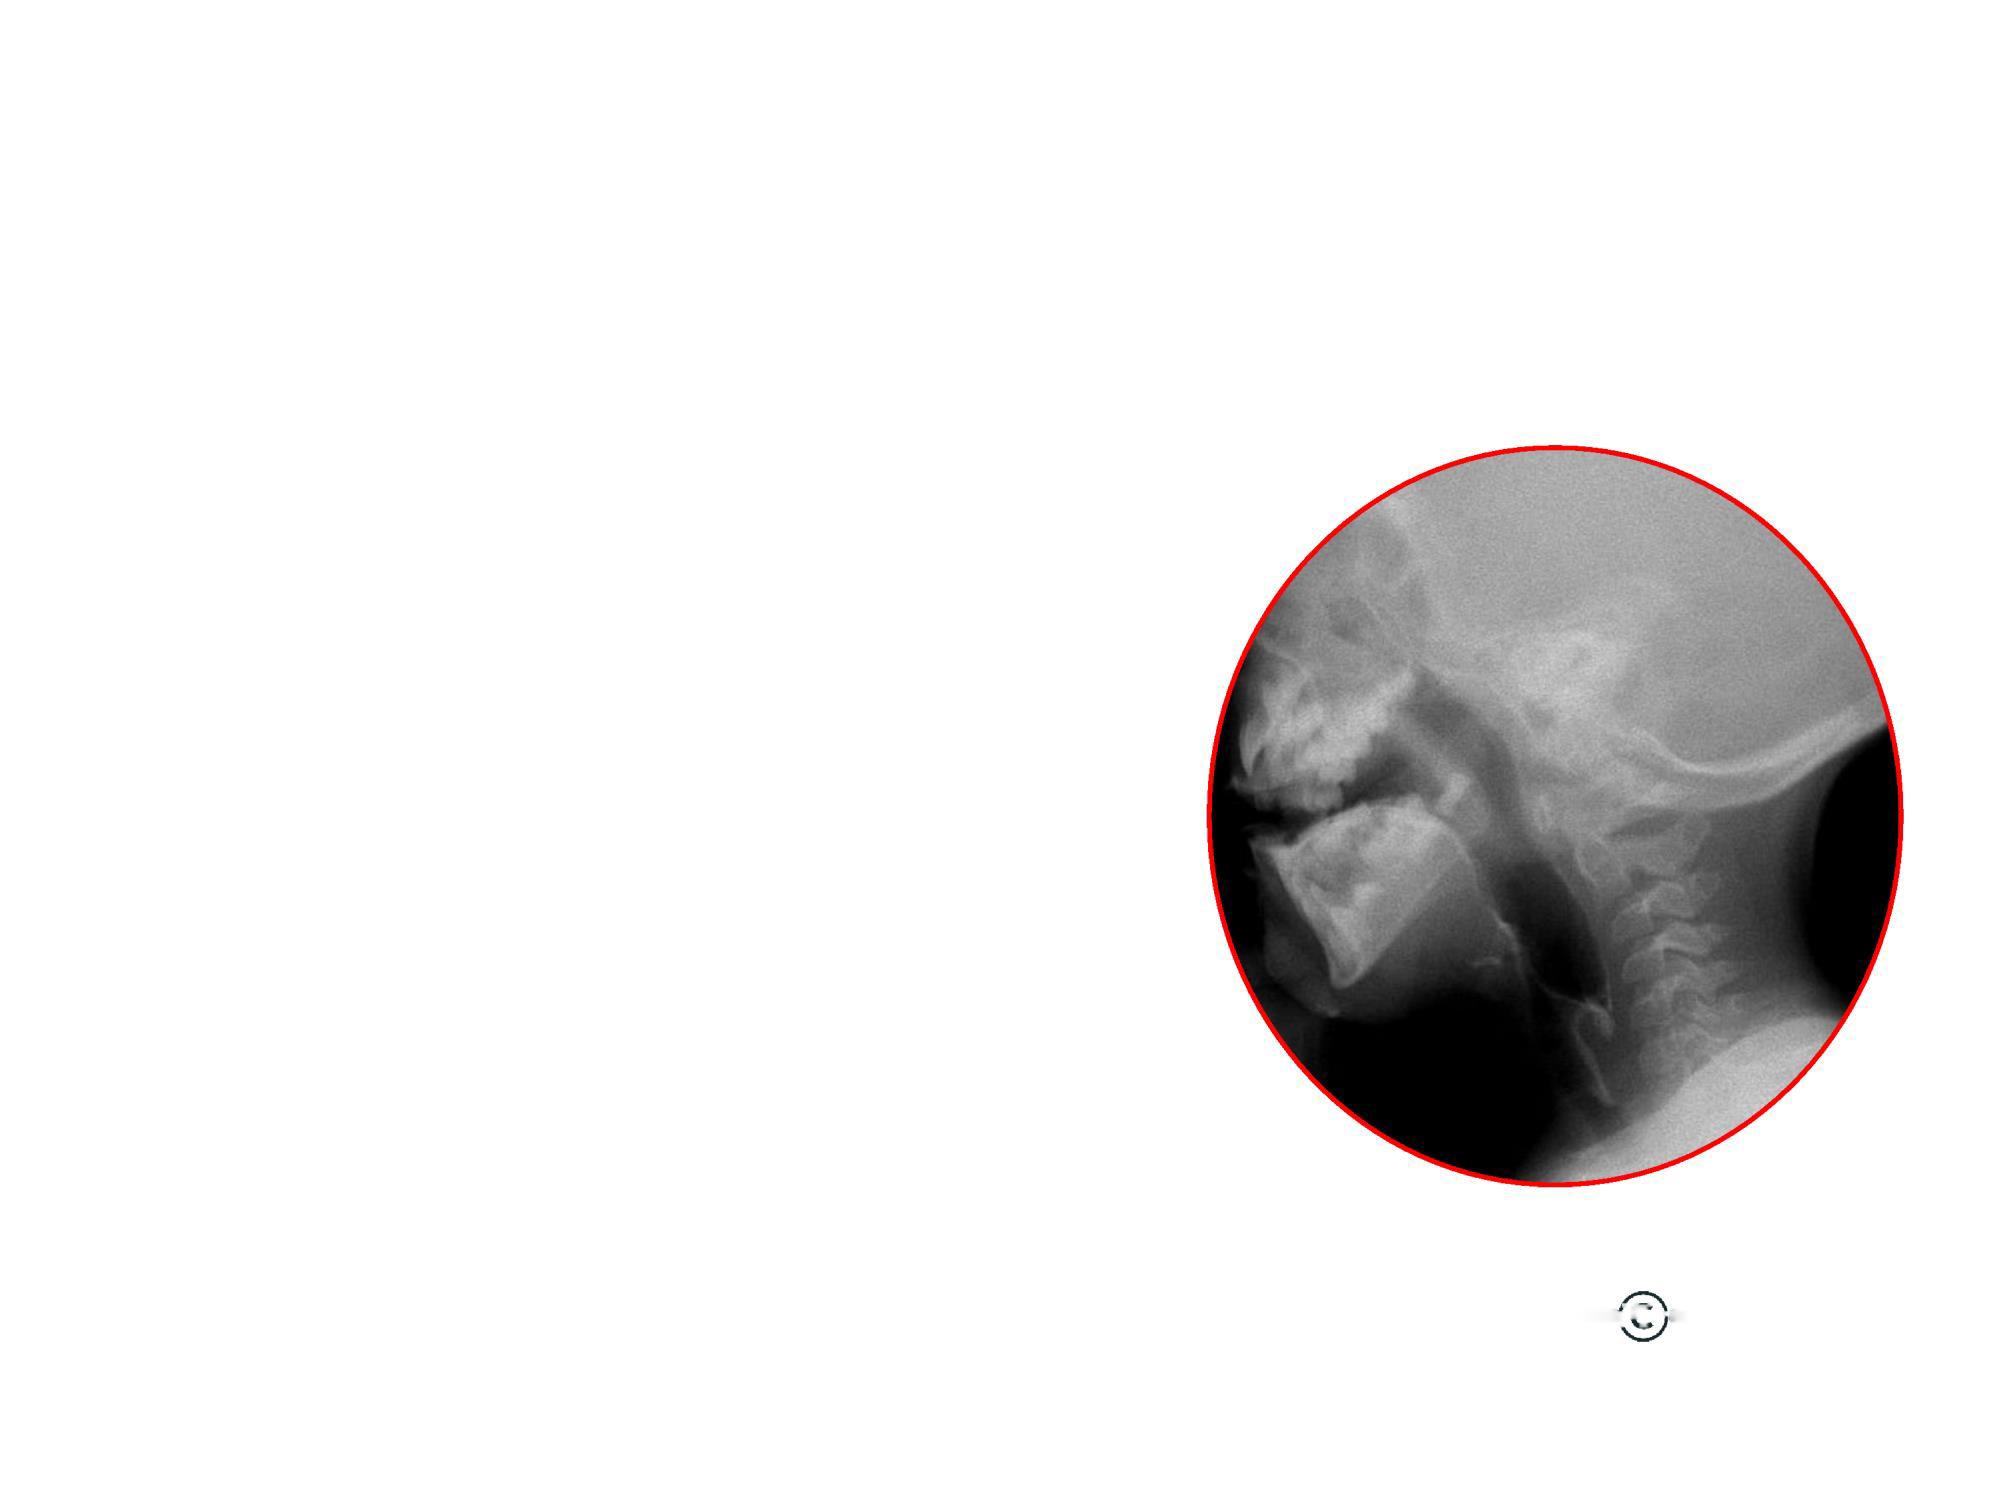

ІНСТРУМЕНТАЛЬНА

Відеофлюороско

пічне

дослідження

ковтання